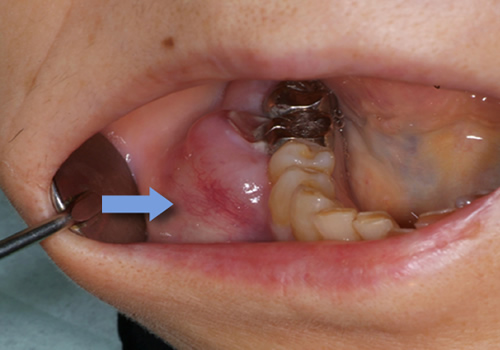

歯肉がん

歯肉に出来る悪性腫瘍は、下顎が多く、有歯顎(歯のある方)臼歯部(奥歯)によく発生します。疫学的には男性が多いです。

無歯顎(歯が全くない方)の患者さんも多いです。口腔に発生するがんの20%弱程度は歯肉がんです。